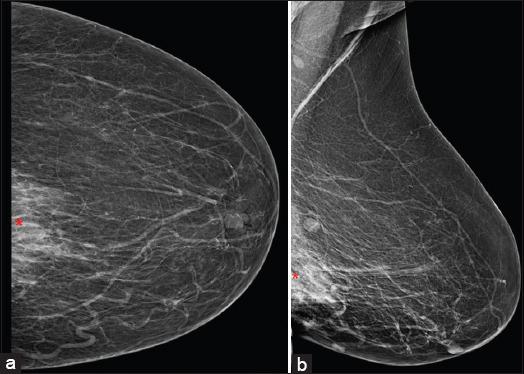

A total of eight cases were identified, out of which seven were females. The most common presentation consisted of the presence of metastatic nodules which were seen in 62.5% (five out of eight) of the patients. Other features consisted of erythematous or plaque-like skin thickening on clinical examination, increased density with indistinct margins seen on a mammogram and diffuse oedematous changes in the skin with small irregular mass or infiltration into subcutaneous tissues were visualised on ultrasound and CT studies.

Skin metastasis from breast cancer most commonly presents as nodules, although rarely they may present as plaques or diffuse skin thickening. Awareness of diverse manifestations of skin metastasis is of utmost importance in early diagnosis and management.